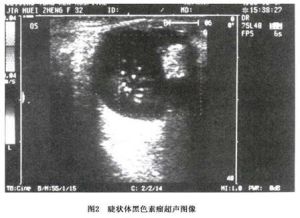

結合彩色超聲都卜勒及B超檢查(圖2)以及鞏膜透照試驗, MRI檢查有利於本病的診斷, MRI顯示T1加權為高信號, T2加權為低信號(圖3)。

圖2 睫狀體黑色素瘤睫狀體黑色素瘤相應區域的鞏膜充血, 血管擴張,部分可見粗大迂曲的血管。累及虹膜角膜角和虹膜時,可見黑色腫物。腫瘤推擠虹膜 腫瘤所在區域虹膜膨隆,前房變淺,腫瘤推擠晶狀體,可致晶狀體移位,或局限性混濁, 甚至完全混濁。散大瞳孔後, 裂隙燈顯微鏡檢查可直接觀察到虹膜後的腫物,多為大小不一、表面光滑的黑色腫物。腫瘤侵犯睫狀上皮,可致低眼壓 侵犯虹膜角膜角小梁網可繼發青光眼。腫瘤發生壞死時前房可有色素游離和沉積,亦可有前房積血、玻璃體混濁、玻璃體積血、滲出性視網膜脫離等, 少部分睫狀體黑色素瘤呈瀰漫性生長,累及整個睫狀體,此種類型較早發生視網膜脫離和眼外蔓延,預後差。部分睫狀體黑色素瘤呈瀰漫性生長, 表現為整個睫狀體區不規則增厚,稱為環狀黑色素瘤(ring melanoma)。腫瘤相應部位的表層鞏膜血管擴張和灶狀色素沉著通常是睫狀體黑色素瘤的重要特徵。